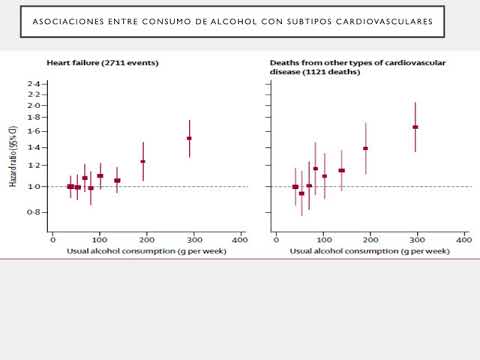

Límites del riesgo de consumo de alcohol. Dra. Ana Laura Mori. Residencia de Cardiología. Hospital C. Argerich. Buenos Aires

Alcohol y riesgo inmediato de eventos cardiovasculares. Dr. Agustín Indavere. Residencia de Cardiología- Hospital C. Argerich. Buenos Aires